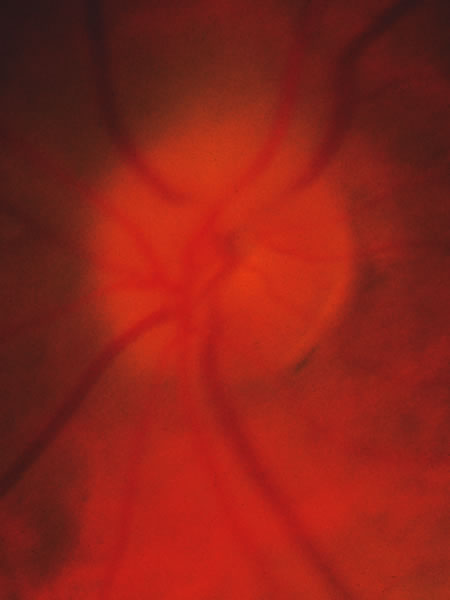

Usually all other forms of optic nerve disease (and inner retinal disease) produce simple atropy of the disc without cupping (Figs. 34 to 36), but occasional cases of cupping have been seen with anterior ischemic optic neuropathy, particularly due to giant cell arteritis (Figs. 37 and 38).

Fig. 34. Photograph of a normal left eye at a time when the right eye had an attack of anterior ischemic optic neuropathy.

Fig. 35. Same eye as Figure 34 during a subsequent attack of ischemic optic neuropathy.

Fig. 36. Same eye as in Figure 34 one year later, with atrophy but no excavation.